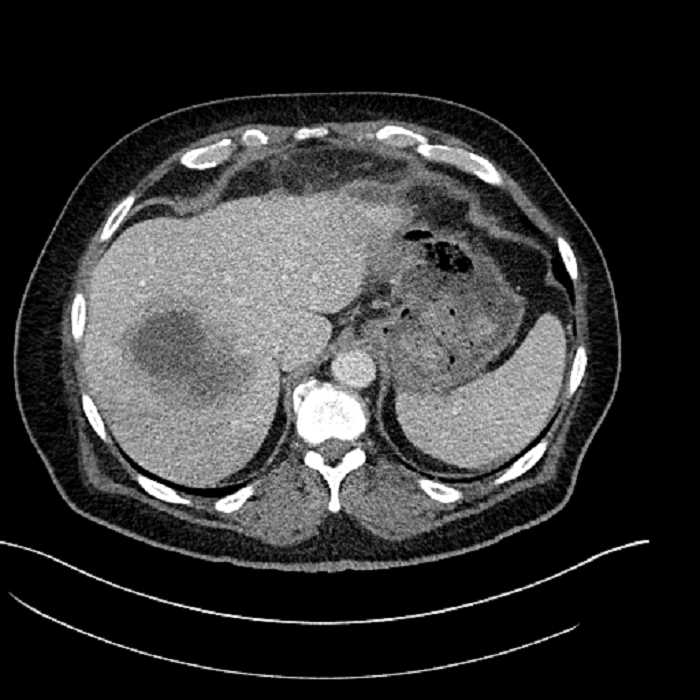

• Large fluid density structure in hepatic segments 7 and 8 measuring 10 x 7 x 7 cm with internal septation and circumferential ill-defined low density compatible with edema

• Peripherally enhancing subcapsular collections along the anterior margin of the left hepatic lobe measuring 3 x 1 cm and 2 x 1 cm

Acute sigmoid diverticulitis complicated by a small contained perforation and a large abscess in the right hepatic lobe. Additional small subcapsular abscesses along the anterior margin of the left hepatic lobe.

• The classic CT imaging appearance is a double target sign with internal low density surrounded by an internal enhancing rim (capsule) and a low density external rim (edema)

Hepatic abscess showing the double target sign with low density internally surrounded by a thin inner enhancing rim (red arrow) and ill-defined outer low density rim (yellow arrow). Blue arrow indicates an internal septation. Red arrows: additional smaller subcapsular abscesses. Red arrow: focal contained perforation associated with diverticulitis.